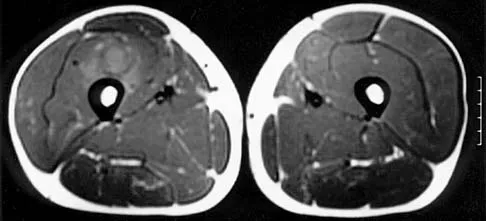

Figures 30a and 30b show the MRI scans of a 51-year-old woman who has had an enlarging soft-tissue mass in her right thigh for the past 18 months. Examination reveals no inguinal adenopathy. Results of a biopsy show a high-grade sarcoma. A bone scan is unremarkable, and a CT scan of the chest shows no evidence of pulmonary metastasis. According to the Musculoskeletal Tumor Society (MSTS) staging system, the tumor should be classified as what stage?

According to the MSTS staging system, soft-tissue sarcomas are staged according to the following factors: grade, site, and metastasis. Roman numerals are used to designate malignant tumors, and Arabic numerals are used for benign tumors. Low-grade malignant tumors are staged as I while intermediate- and high-grade tumors are staged as II. Site is defined as intracompartmental (A) or extracompartmental (B). Any metastasis is staged as III. This patient has a high-grade tumor (II), and the MRI scans show that it is confined to a single compartment; therefore, it is staged as IIA. There is no evidence of metastatic disease. Enneking WF, Spanier SS, Goodman MA: A system for the surgical staging of musculoskeletal sarcoma. Clin Orthop 1980;153:106-120. Peabody TD, Monson D, Montag A, Schell MJ, Finn H, Simon MA: A comparison of the prognoses for deep and subcutaneous sarcomas of the extremities. J Bone Joint Surg Am 1994;76:1167-1173. Pisters PW, Leung DH, Woodruff J, Shi W, Brennan MF: Analysis of prognostic factors in 1,041 patients with localized soft tissue sarcomas of the extremities. J Clin Oncol 1996;14:1679-1689.